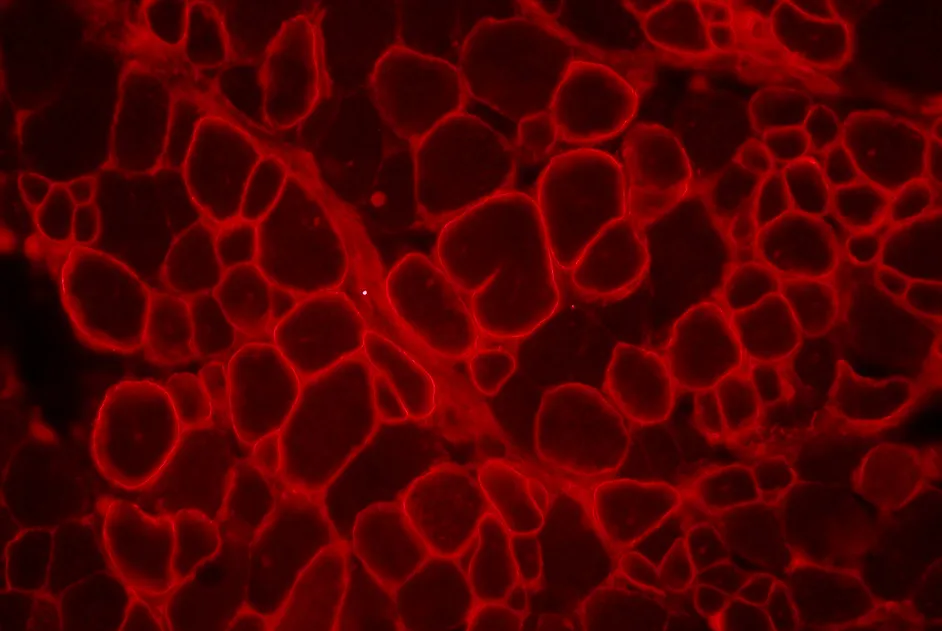

Une thérapie génique avec de nouveaux AAV-calpaïne 3 améliore les symptômes de souris modèles de LGMD2A sans être toxique pour leur cœur.